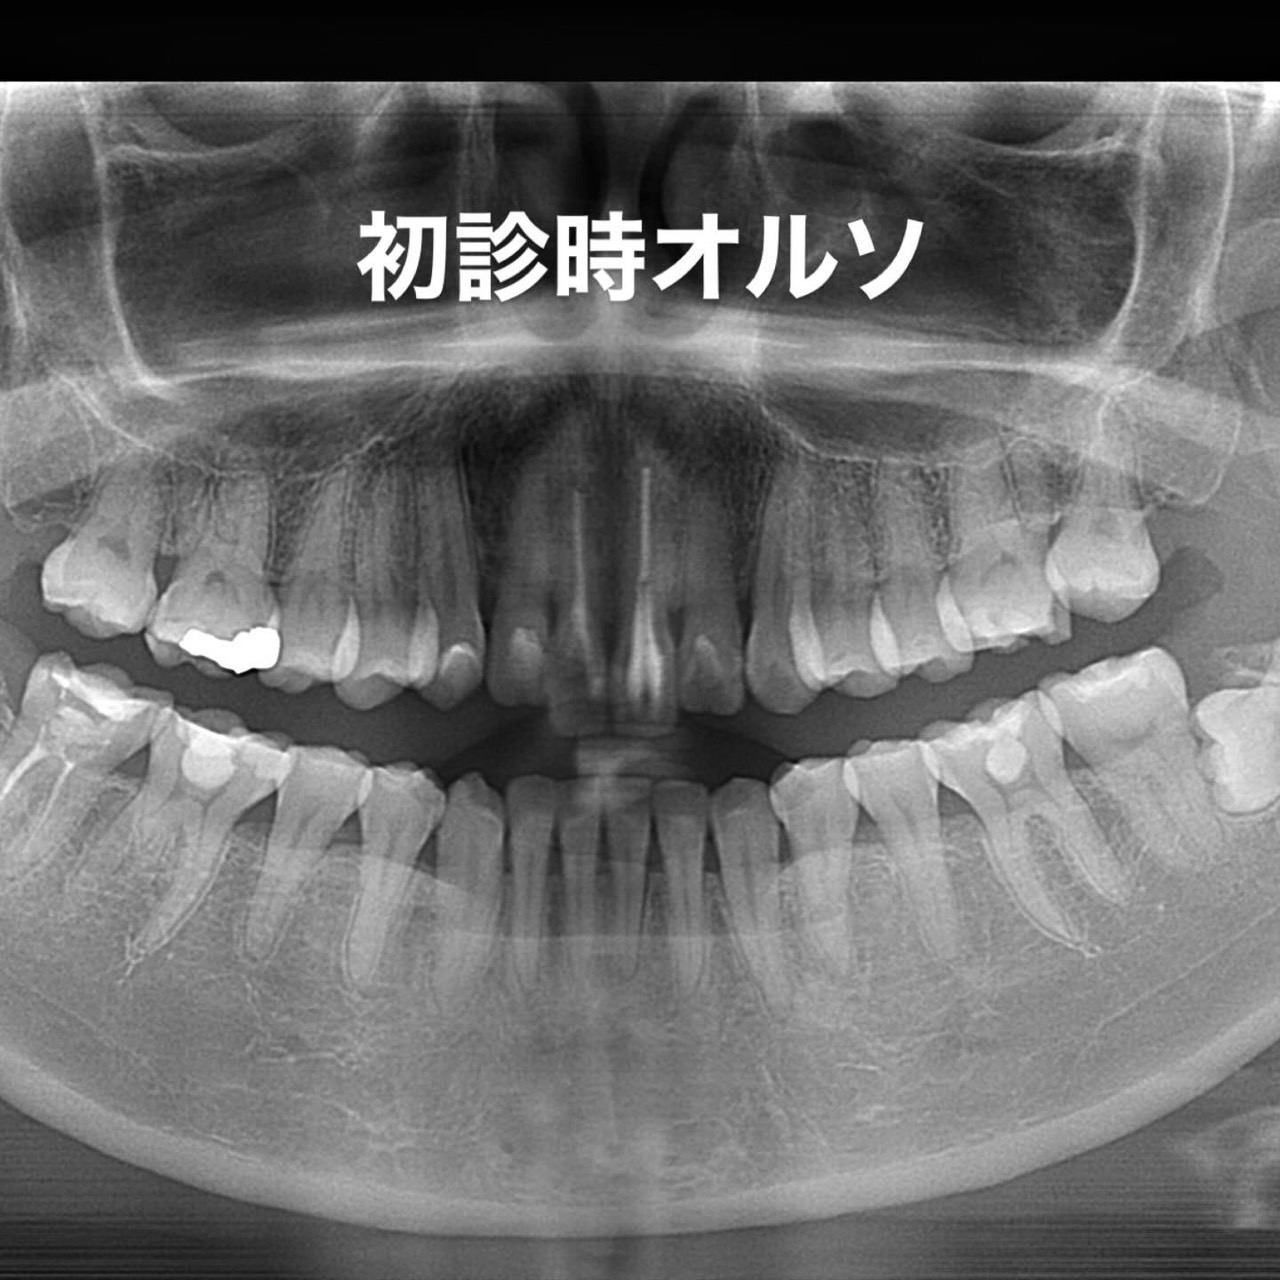

Case022 – インプラント

広島からの患者様です。

前歯を綺麗にしたい。インプラントをしたい。

という主訴で東京の歯医者をいろいろ調べて当院を選んでくださいました。

毎回、遠い中しっかり通ってくださり、選んで頂けた嬉しさと、その気持ちに応えたいという想いで診療させて頂きました。

前歯はご希望のお色でラミネートベニアでは出せない透明感のあるセラミックに上下左側7はインプラントをさせて頂きました。

左上は破折で温存不可。

骨も少なかったので、サイナスリフトも行い計五回の来院で被せ物を入れさせて頂きました。

左下は前回のクリニックでの埋入位置が深すぎて食べカスも毎回詰まる、セルフメンテナンスではら汚れも取れない。インプラント周囲炎にもなっていたので、一度前のインプラントを除去し、そこから新しくインプラントを埋入し、診療させて頂きました。